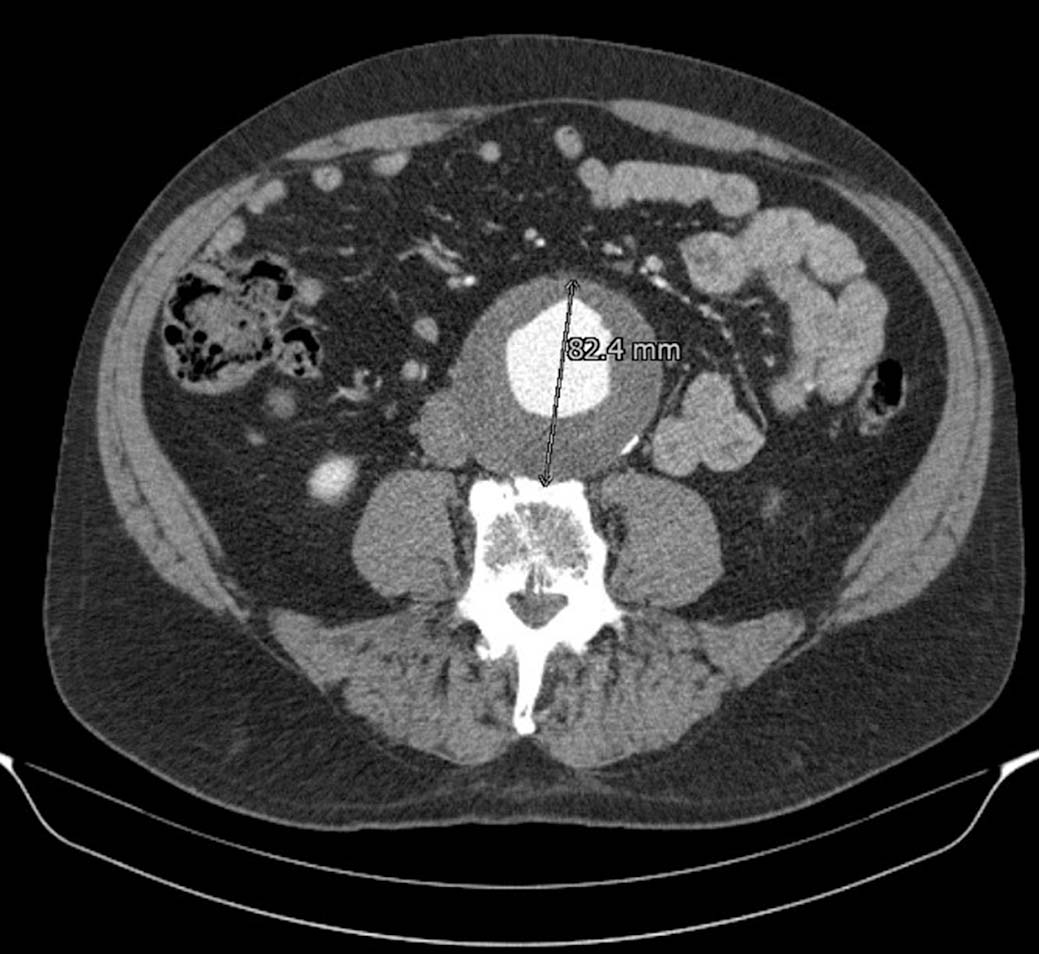

De patiënt werd nadien niet gevolgd. In 2018 werd de man door de huisarts verwezen voor echografie in verband met sinds drie maanden bestaande buikpijn. Op de echo werd een AAA van ruim 7 cm ontdekt; op de daarna gemaakte CT-aorta bleek de diameter zelfs 8,2 cm [figuur 2]. Bij een zodanige verwijding is het risico op een aortaruptuur groot. Gelukkig kon deze patiënt nog op tijd worden behandeld en de endovascular aneurysma repair (EVAR) verliep zonder complicaties.

Figuur 2 | Dezelfde patiënt in 2018: diameter 8,2 cm

Ook de groeisnelheid van een aneurysma wordt als een risicofactor beschouwd. Gemiddeld groeit een ‘klein’ aneurysma (van 3,0 tot 5,4 cm) met 0,22 cm per jaar, maar naarmate het aneurysma groter wordt, neemt de groeisnelheid toe.910 Een aneurysma van 3 cm groeit bij mannen met gemiddeld 0,13 cm en bij vrouwen met 0,15 cm per jaar, een aneurysma van 5 cm groeit bij mannen én vrouwen met gemiddeld 0,36 cm per jaar.10 AAA’s met groeisnelheden van ≥ 1 cm per jaar worden over het algemeen beschouwd als snelgroeiend.6 Er is anekdotisch bewijs dat de kans op een ruptuur groter is bij snelle groei.6 Snelle groei zou een teken kunnen zijn van verhoogde druk of van een verzwakte aortawand. Daarom moeten patiënten met een snelgroeiend aneurysma worden verwezen naar de vaatchirurg. Aangezien het aneurysma bij onze patiënt snel gegroeid was en een diameter had van 8,2 cm, was het risico op een ruptuur voor hem mogelijk nog groter dan de genoemde 6,3% per jaar.